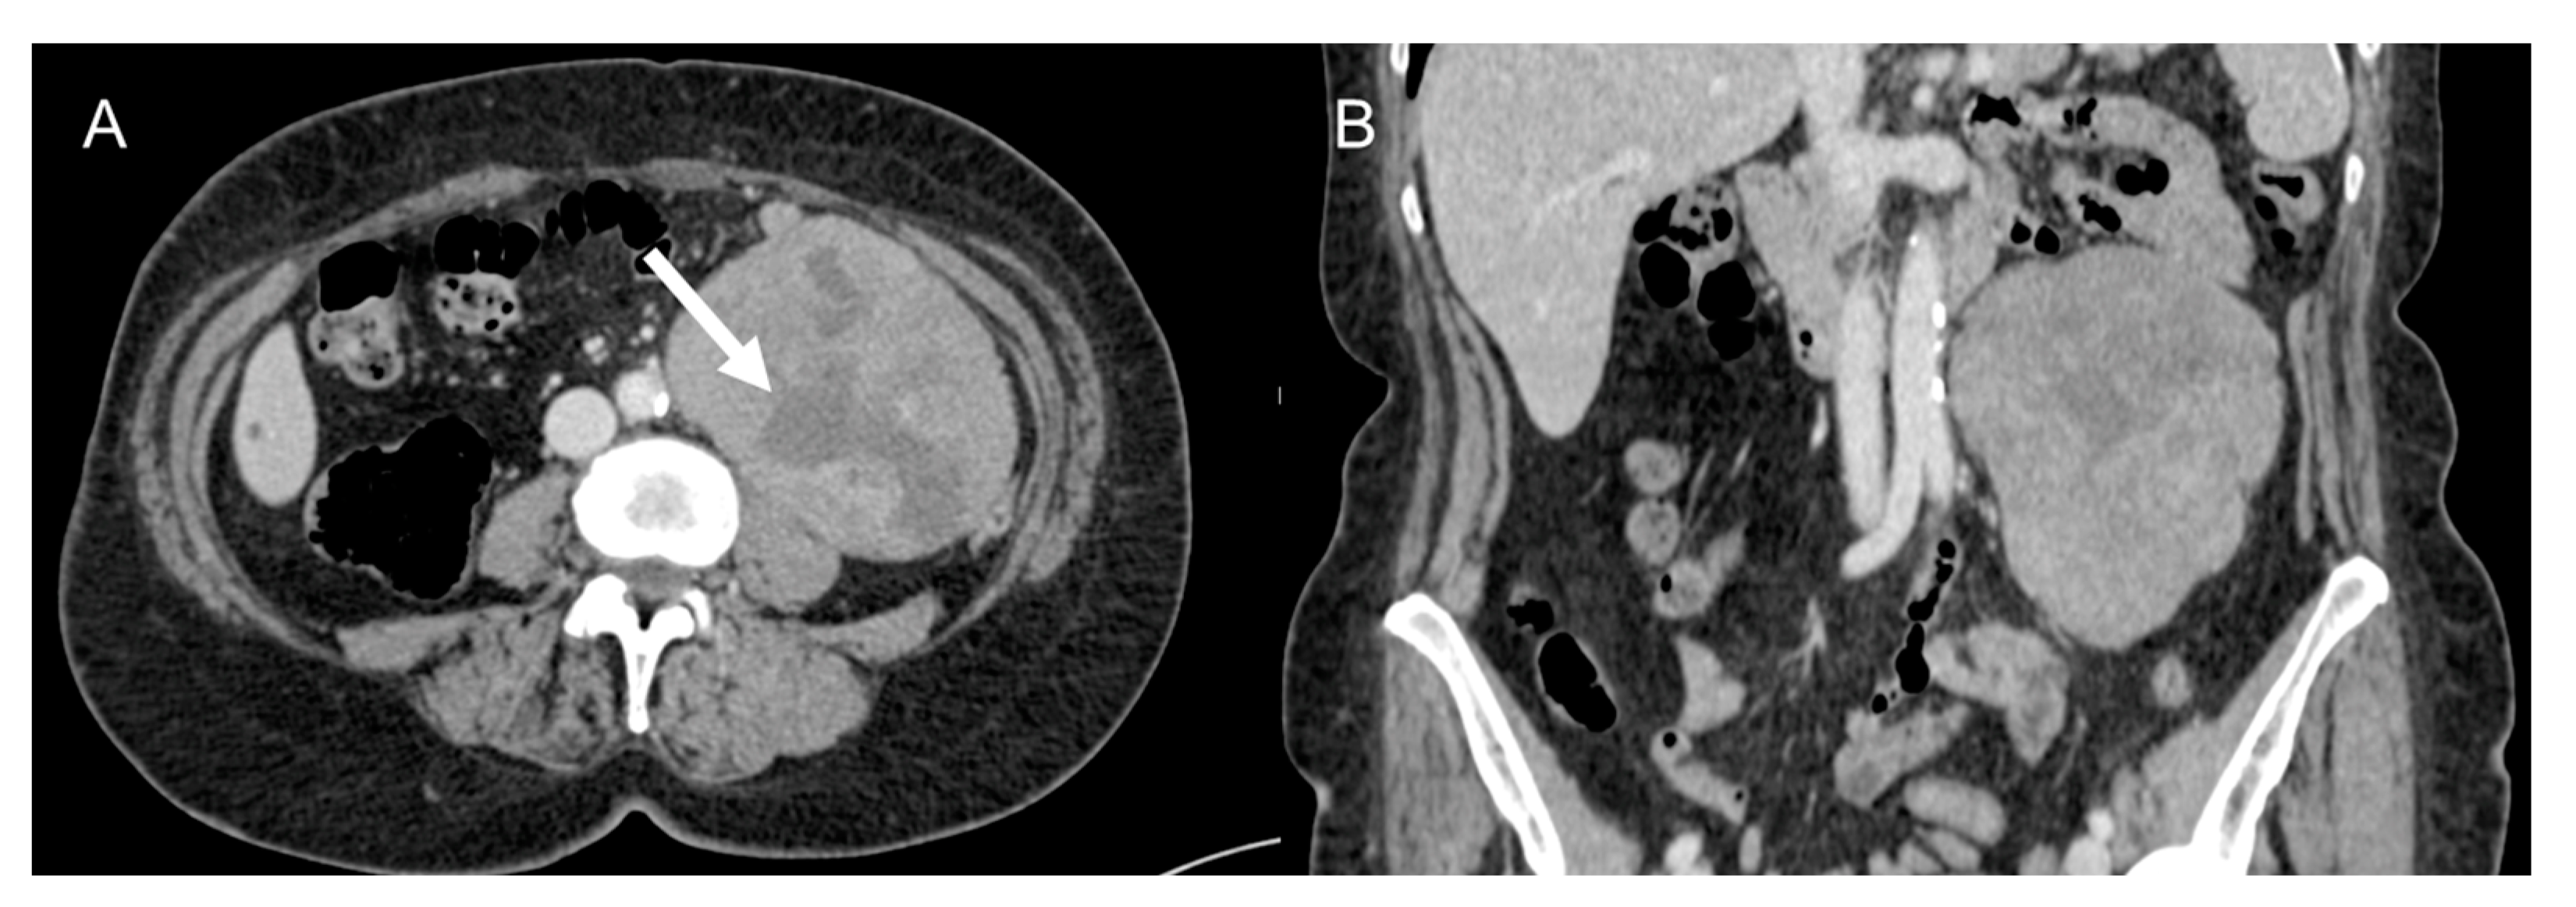

5. Complications

Complications are usually related to tumor invasion of adjacent structures or to mass effect caused by the tumor and include hydronephrosis, pulmonary embolisms secondary to compression of inferior cava vein, nerve compression, bowel obstruction (Figure 11) [49], and even intestinal perforation [50]. Postoperative complications are divided into early and late complications and include pulmonary embolism, ileus, fluid collections, hemorrhage [49], splenic injuries, sepsis, multisystem organ failure. For these reasons, guidelines recommend that immediate postsurgical care should be held in subspecialized facilities [2,19,51,52,53].

Figure 11.

Bowel obstruction in 38-year-old woman with metastatic leiomyosarcoma. Axial (A,B) and coronal (C) CT images on the venous phase show dilatation of small bowel loops with air–fluid levels secondary to the presence of metastatic masses (arrow) in the pelvis.